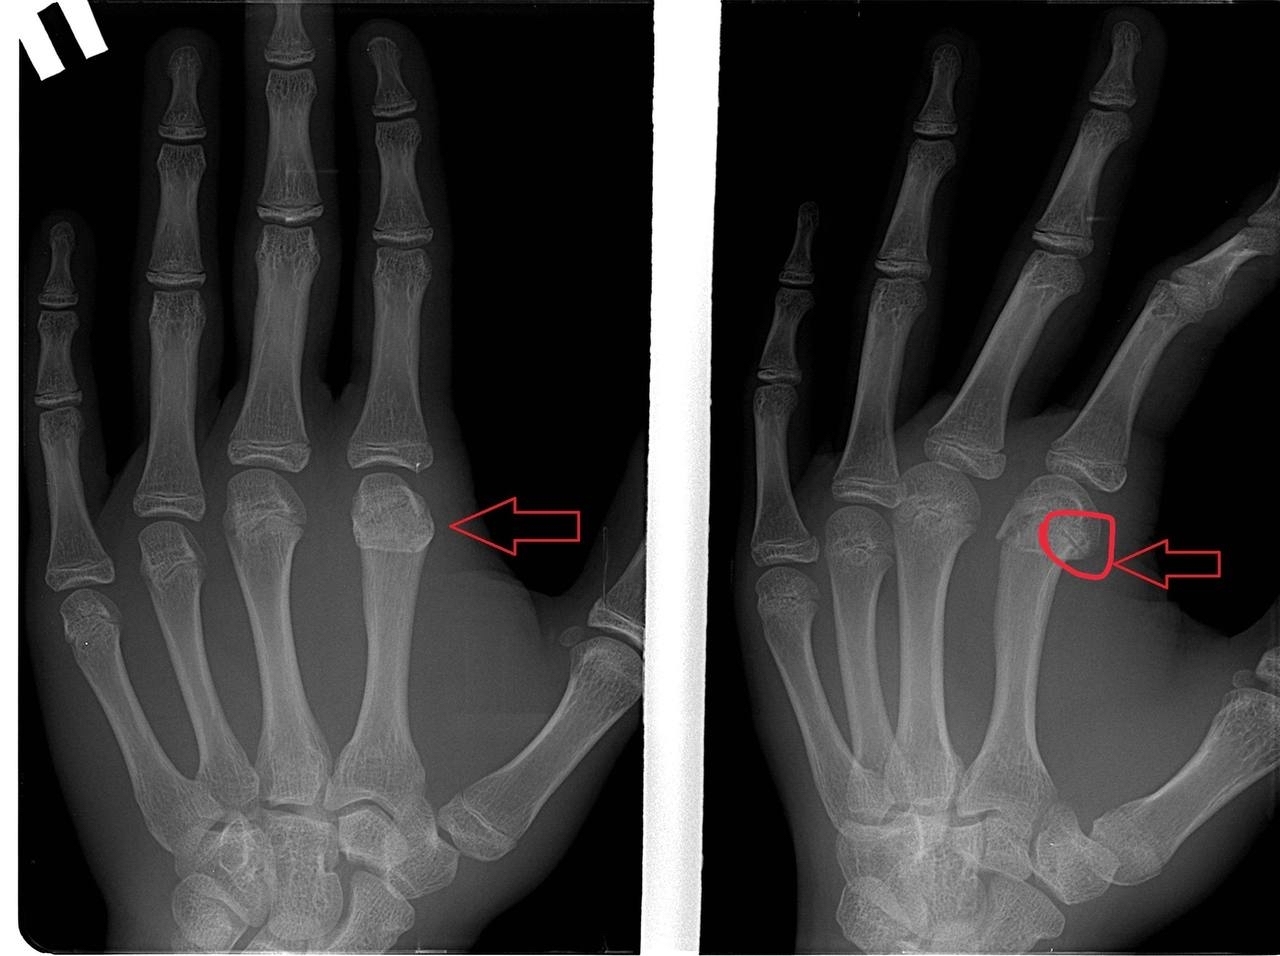

Док,а тут чего?

Иллюстрация к комментарию

Головка 2 пястной сломана